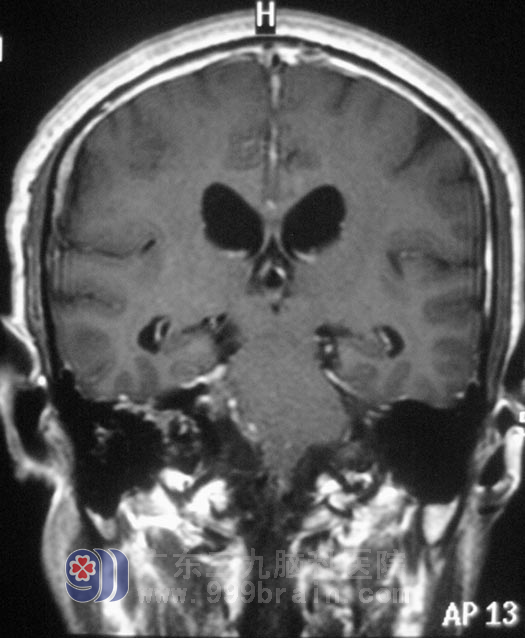

区先生,今年44岁。五年前开始出现右耳听力下降,间断头晕,呈阵发性,当地医院考虑是五官科问题,予对症治疗后症状无明显好转,且右耳听力下降不断加重。三个月前,他逐渐出现双眼视力下降,间断头晕伴有恶心感。头颅CT检查,结果提示“右侧桥小脑角区占位,约3.5cm×3.2cm,考虑听神经瘤,伴梗阻性脑积水”。

入住广东三九脑科医院综合神经外科时,区先生左侧侧鼻唇沟变浅,露齿时口角向右侧歪斜,双耳听力下降(右耳明显),闭目难立征(+),易向右侧倾倒。12月20日,由鲁明主任主刀,在全麻下行右侧乙状窦入路听神经瘤切除术。术中显微镜下见黄白色肿瘤组织,位于右侧桥小脑角区,质软,血供丰富,面神经位于肿瘤前下方,副神经、迷走神经、舌咽神经位于肿瘤后下方,神经组织形态菲薄,在显微镜下用超声刀分块切除,磨钻磨除部分内听道,切除内听道内肿瘤组织,中后组颅神经保护完好,手术顺利结束。术后病理结果为:(右侧桥小脑角)神经鞘瘤。